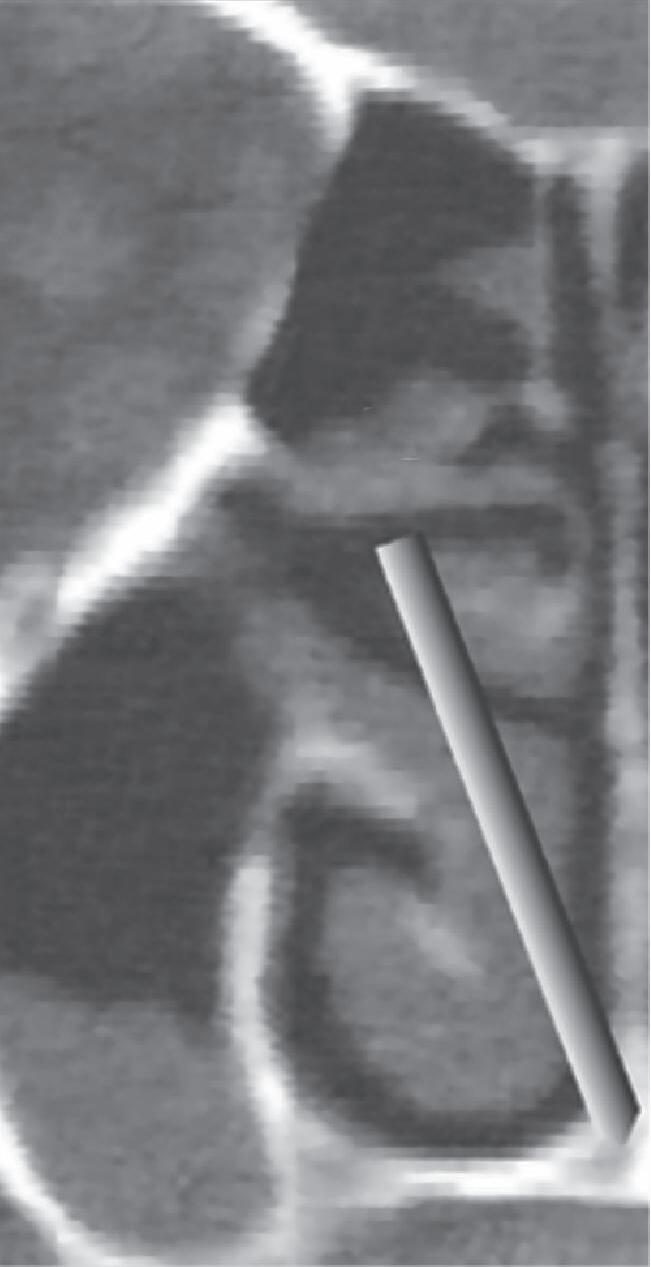

1-13. Montagem em aspecto endoscópico e peça anatômica (Bagatella) demonstrando a relação do processo uncinado e bulha etmoidal com a parede medial da órbita: (1) porção meatal da concha média; (2) processo uncinado; (3) bulha etmoidal; (4) parede medial da órbita.

1-16. Relação da bulha etmoidal com a órbita em corte axial, coronal e sagital, respectivamente.

A bulha etmoidal lembra a forma de uma meia-lua e se encaixa na parede medial da órbita (lâmina papirácea) criando, posterossuperiormente (em sua relação com a porção vertical da lamela basal), um recesso algumas vezes chamado de seio lateral e outras de recesso suprabulhar, onde se abrem a própria bulha e cavidades etmoidais vizinhas.

Posterior à bulha etmoidal encontra-se a principal estrutura que fixa a concha média na órbita e na base do crânio: a lamela basal. Esta lamela, como a própria concha média, é oblíqua em relação à lâmina papirácea tanto no sentido anteroposterior como no superoinferior e delimita posteriormente a câmara anterior.